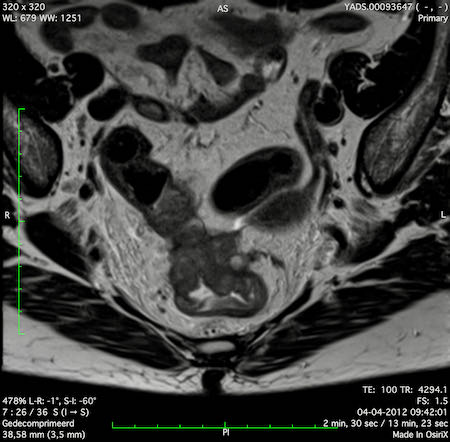

Hình ảnh

Các hình ảnh được cung cấp cho thấy ung thư biểu mô tế bào nhẫn với tình trạng dày lan tỏa thành trực tràng, hình ảnh bia bắn điển hình, và sự xâm lấn mỡ mạc treo trực tràng.